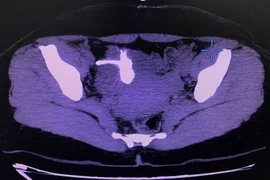

Sỏi thận và sỏi tiết niệu

(khoahocdoisong.vn) - Sỏi thận, sỏi tiết niệu là bệnh rất phổ biến trên thế giới, đặc biệt là ở Việt Nam. Theo thống kê, tỷ lệ điều trị bệnh sỏi tiết niệu (sỏi thận, sỏi niệu quản, sỏi bàng quang, sỏi niệu đạo) tại khoa thận – tiết niệu chiếm trên 40%.